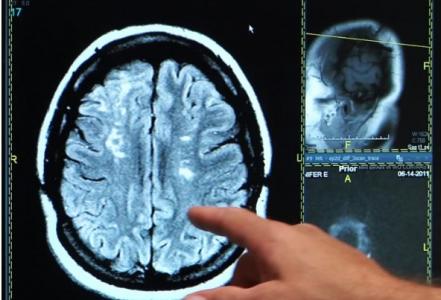

Ce nouveau programme informatique développé par des scientifiques des universités d'Édimbourg et de Glasgow permet d'évaluer la détérioration du cerveau et de prédire la fonction cognitive après un accident vasculaire cérébral (AVC) jusqu'à 10 fois plus précisément que les méthodes actuelles. Ce développement, présenté dans l'International Journal of Stroke, permet ainsi de quantifier les lésions cérébrales visibles des vaisseaux cérébraux et l'atrophie cérébrale en analysant plus d'un million de données stockées dans les scintigraphies cérébrales en une seule mesure : ce nouvel index.

Une analyse fine des données de scintigraphie : actuellement, les scintigraphies cérébrales aident les médecins à savoir quand l’AVC s'est produit, et contiennent également des données précieuses permettant d’évaluer le risque, pour un survivant d’AVC de développer des troubles cognitifs ou la démence. Cependant, jusque-là, la plupart des méthodes informatiques actuelles ne prenaient pas en compte tous les facteurs disponibles. C'est ce qui a conduit le Pr Joanna Wardlaw, de l'Université d'Édimbourg et son équipe à développer cet index de santé cérébrale.